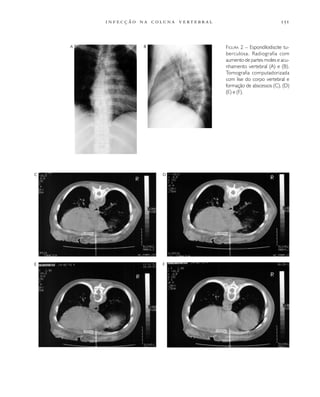

Densidade mineral óssea 96

Densitometria 181